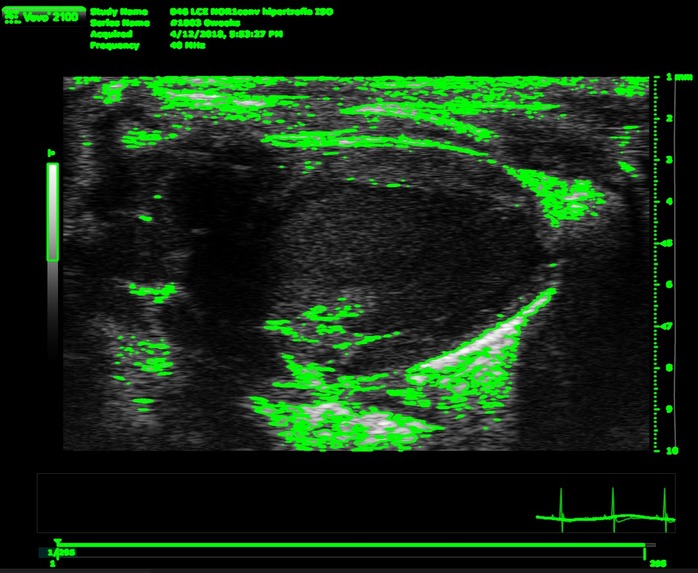

Its a CLI's program where have to give a psla and sax dicom files path. Then gets some variables from the files to throw some conclusions (if it's a healthy heart or not) and also it save it as excel file.

We built it as a python project with its virtual environment with the requirements needed, also needs a special program called Theseract that it is a optical character recognition open source to get the BPM from the files, the rest of the needed parameters are calculed using opencv mainly.

The most significative challenge that the team ran into consisted in the identification of the contourns of the image. Differenciating between the underside and the outer layer of the blood vessel ended up being an arduous task